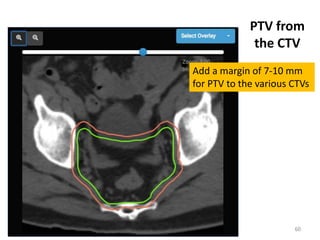

Add a margin of 7-10 mm

for PTV to the various CTVs

PTV from

the CTV